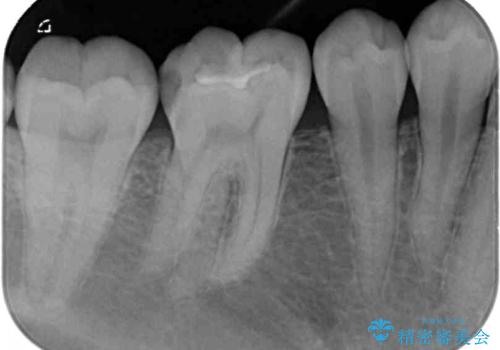

- 右下の奥歯が噛んだ時に痛み、冷たいものがしみることを主訴として来院された患者様です。

精査の結果、歯が欠けていてその下に虫歯が認められました。

また、咬合面(歯の噛む面)に以前治療した樹脂の詰め物があるため、一度外して虫歯を完全に除去し、

精度の高いセラミックインレーにて修復処置することとしました。